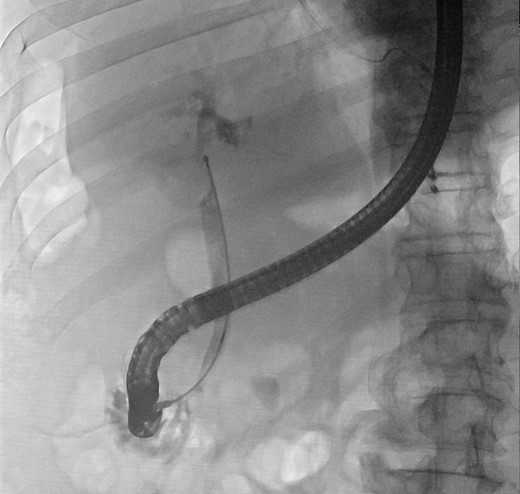

We report a case of a 67-year-old man, who presented with fever, chills and jaundice to a local district hospital. He had a temperature of 39°C and new-onset atrial fibrillation. Examination of the abdomen showed no peritoneal signs. Blood biochemistry demonstrated leukocytosis and abnormal liver function tests: bilirubin 75 μmol/L, alkaline phosphatase 1018 unit/L, alanine transaminase 177 unit/L. Ultrasound scan showed a 3 cm gallstone without common bile duct dilatation. However, computed tomography of abdomen revealed a gallstone eroding into the CHD, causing intrahepatic ductal dilatation (Fig. 1). The diagnosis of type II Mirizzi syndrome was confirmed by endoscopic retrograde cholangiopancreatography (ERCP), where cholangiogram demonstrated a gallstone fistulating into the CHD (Fig. 2). Biliary stent was inserted and intravenous antibiotics were given to tie over this acute episode of cholangitis.

Cholangiogram demonstrating filling defects at the common hepatic duct.

In view of his multiple medical comorbidities, which included obesity, hypertension, hyperlipidemia, ischemic heart disease with history of percutaneous transluminal coronary angioplasty, obstructive sleep apnea and sick sinus syndrome, he was considered a poor candidate for definitive surgery. Therefore, after the index cholangitic episode had settled, he received further endoscopic treatment. A combination of endoscopic papillotomy, biliary stenting and mechanical lithotripsy (ML) was adopted. After a total of eight additional sessions of ERCP, with repeated stent exchange, stone clearance was achieved. He was well and discharged with cleared ducts. Long-term stenting was not required.